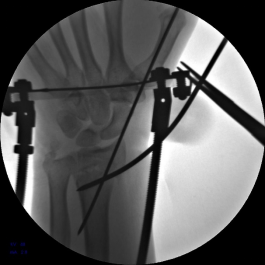

6.六轴机器人撬拨骨块过程

7.手术完毕,复位满意